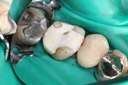

Wayne Chin #14 prep